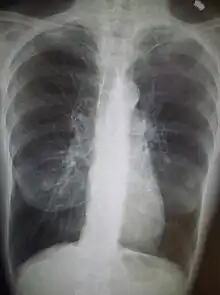

Examens complémentaires

- Radiographie pulmonaire pour les épisodes aigus ;